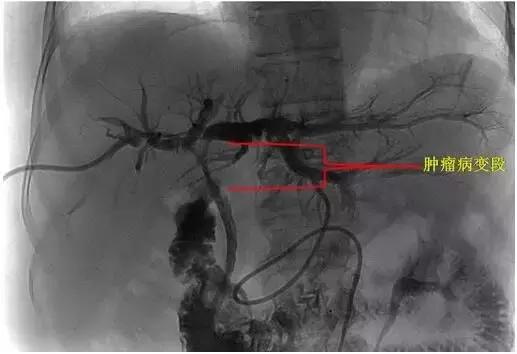

术中DSA下示意图:

1、 肿瘤病变狭窄段